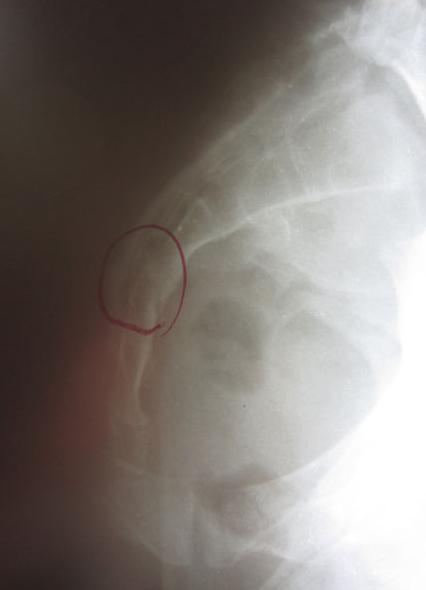

Miss C不慎由楼梯摔落直接跌坐在屁股上,在尾椎骨持续疼痛数天之后由医师评价发现有尾骨骨折裂伤的情况。当下给予止痛药与肌肉松弛剂作为治疗。但疼痛状况却未见明显改善。经评价发现骨盆有严重歪斜的状况,在调整骨盆歪斜的问题之后疼痛状况大幅改善,可完全不需止痛药。三个月后回诊医师判定尾椎骨折部位愈合良好。